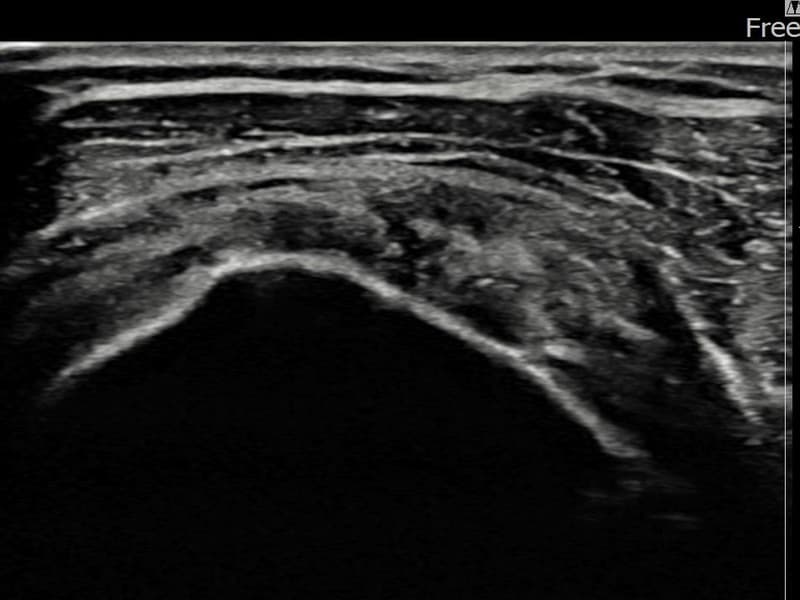

术后

术前超声确认左侧 冈上肌腱 关节面侧部分撕裂,左侧冈上肌腱回声不连续伴肌腱缺损(3.5mm × 3.1mm (부분파열))。术后超声显示撕裂部位充满再生组织,肌腱连续性恢复,回声模式正常化。

该患者持续肩痛。详细超声检查确认左侧 冈上肌腱 关节面侧部分撕裂(缺损:3.5mm × 3.1mm (부분파열))。在超声引导下实施非手术缩小缝合术。术后佩戴支具约4-6周,随后进行分阶段康复锻炼。随访超声确认肌腱连续性恢复、结构稳定,患者顺利回归日常生活。